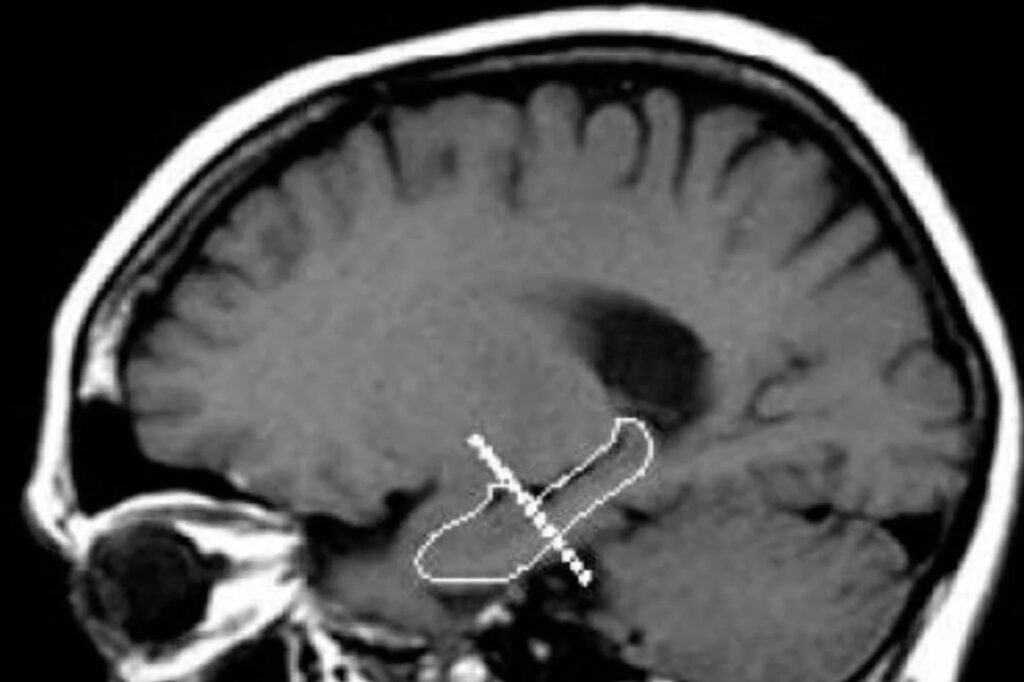

Marta Portero, profesora e investigadora del Instituto de Neurociencias de la UAB (INc-UAB) y primera autora del estudio, le explicó que el estudio investigó, en concreto, el efecto de una dieta baja en calorías en el hipocampo, estructura fundamental para aprendizaje, recuerdos y memoria reciente y orientación. «Y los resultados han corroborado que sí se da una mejora cognitiva derivada de la dieta hipocalórica y que va ligada a una reducción de los niveles de inflamación y a una menor pérdida neuronal en el hipocampo».

Hipocampo. Foto cortesía Diario Médico